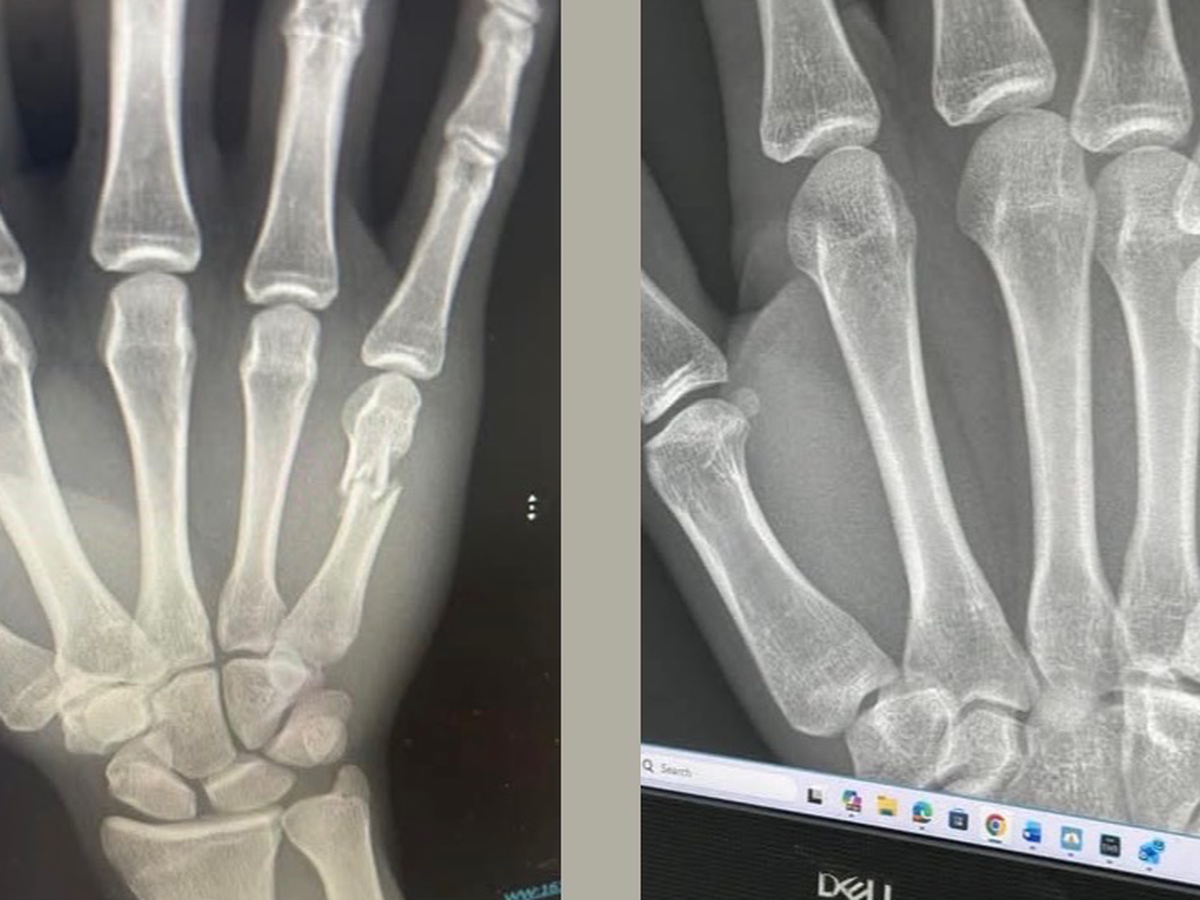

Two weeks ago I broke my hand and the following week I found out that the bone I broke is now shifting and I am in need of surgery. Or it will not heal right

In order to go to the military. I need to have surgery and be medically cleared if I do not get the surgery, the military is out though question because they are saying that it will heal wrong and I won’t have full motion in my hands, nor will I be able to grip things properly.